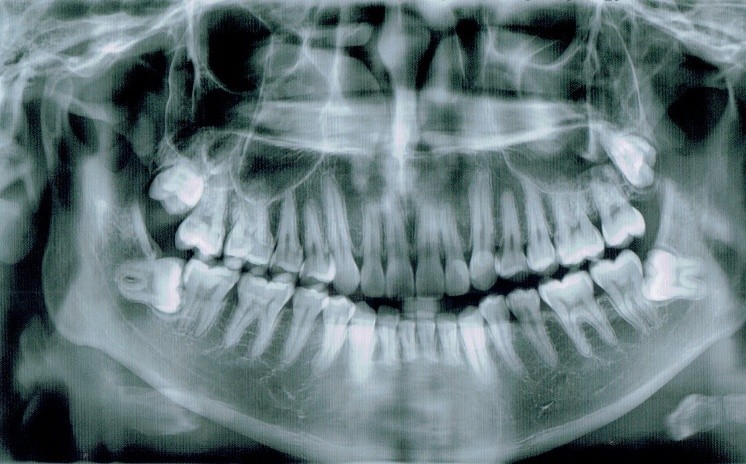

Tooth 4.8 is planned for extraction. Which radiographic findings suggest an increase in the degree of difficulty of the extraction?

Tooth 2.8 is planned for extraction. Which radiographic findings suggest an increase in the degree of difficulty of the extraction?

Tooth 1.8 is planned for surgical extraction. Which radiographic findings suggest an increase in the degree of difficulty of the extraction?

Tooth 2.8 is planned for surgical extraction. Which radiographic findings suggest an increase in the degree of difficulty of the extraction?